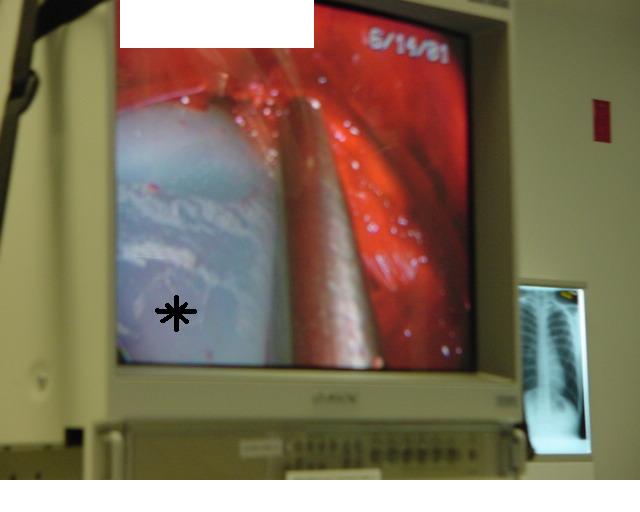

Once the tunnel reaches the sternum, the endoscopic tunneling device is utilized to visualize the clamp entering the interspace of maximal pectus depth and passing retrosternal (Figure 7). At the level of the sternum, these tunnels go retrosternal and communicate with each other. Ideally, even after entering the interspace, the tunnel stays extrapleural. The endoscopic view of the tunnel allows visualization of the safe passage of the clamp under the sternum and anterior to the pericardium. The mediastinum and pericardium can be seen pulsating posterior to the clamp. Two monitoring screens are utilized in order to allow excellent visualization by both the surgeon and assistant (Figure 8). Eventually, the larger curved clamp is easily passed under the sternum (Figure 9). This clamp is thus passed through one midaxillary skin incision and out the other midaxillary skin incision.

The two incisions, each less than one inch long, are then closed with absorbable monofilament sutures (Figure 15). A chest X-ray is performed in the operating theater to document satisfactory bar position and evaluate for pneumothorax. The post-repair anatomy is documented with photography in the AP plane (Figure 16) and lateral plane. Patients are extubated in the operating theater.